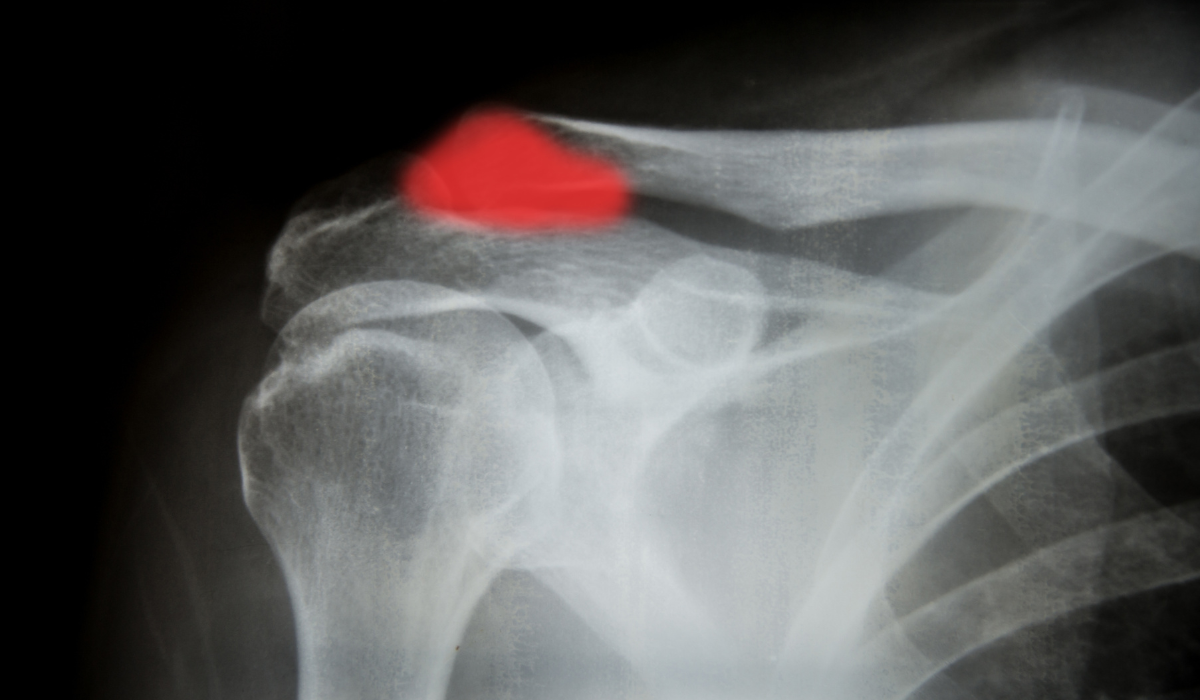

A fractured shoulder or broken shoulder can be either displaced or non-displaced. When the broken pieces are still in their anatomic position, it is described as a non-displaced fracture. Displaced shoulder fracture requires restoring the shoulder to its normal anatomy. Proximal humerus fracture, fractured scapula, and fractured clavicle are the different types of shoulder fractures.

Shoulder fractures are the traumatic events resulting from a fall on the shoulder, accidents, contact sports, etc. The shoulder is a complex joint connecting the upper end of the humerus with glenoid (socket of capsule). Any disturbing event or rupture in these parts results in fractures and can affect the functioning of the shoulder.

Once your diagnosis is confirmed, the doctor will discuss the treatment options that best fit you. However, the treatment options vary depending on the type and severity of the fracture.